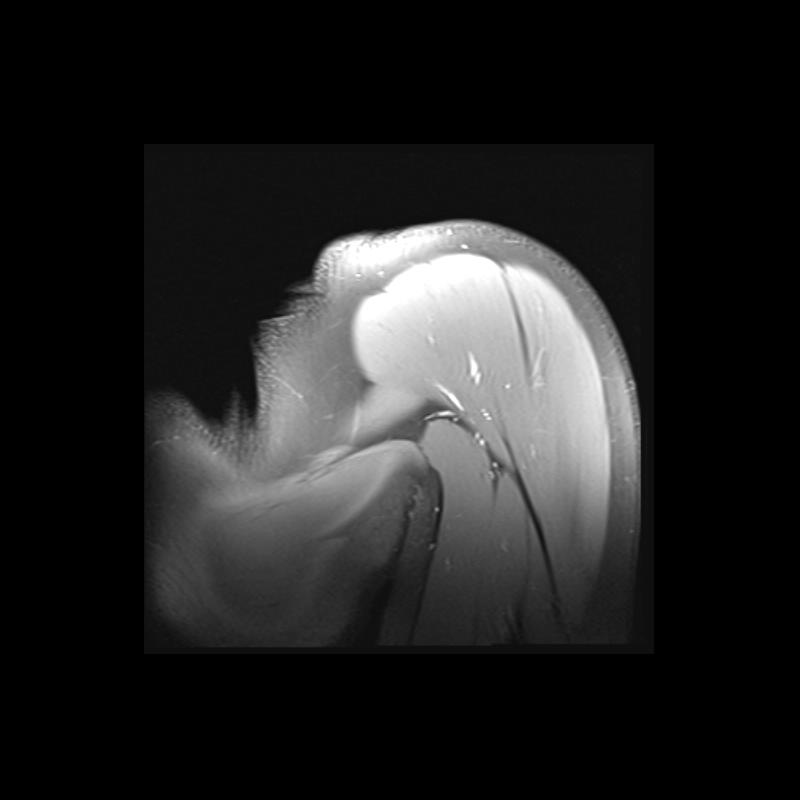

Shoulder MRI Anatomy